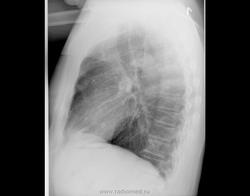

Fujimi, Вы - умница! Чужой - действительно паразит. К нам пациента направили с диагнозом "мтс в кости и легкие". Уж как удивился морфолог, увидев "чужого под микроскопом! Здесь картина очень редкая и потому ни на что не похожая. Но по легким догадаться можно.

Ваш акцент сделанный на "лёгкие", конечно направляет вектор в сторону туберкулёза.

Хотя "туберкулёз" в легких мало на туберкулёз похож.